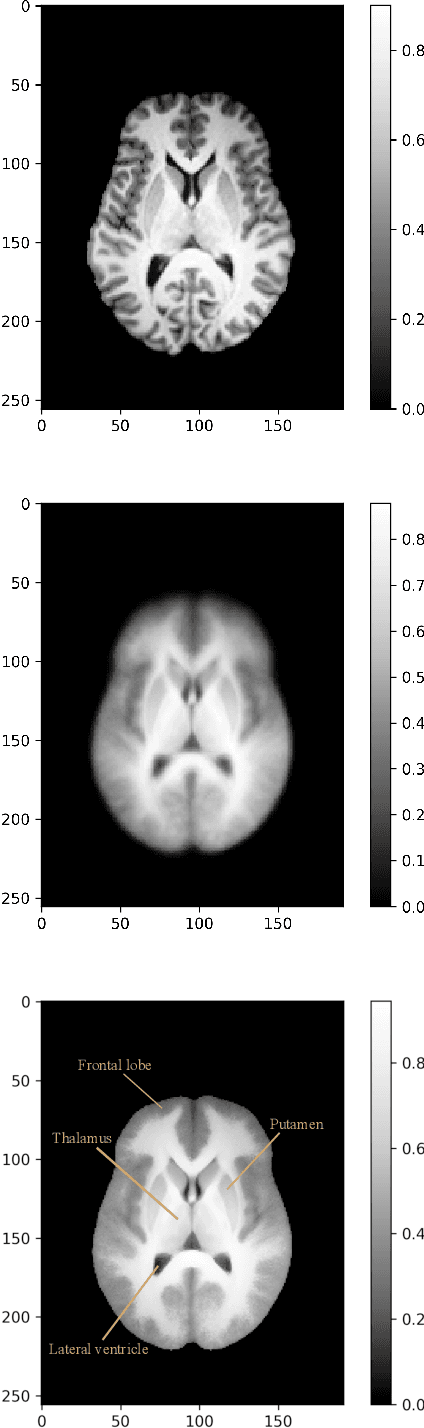

Abstract:In many image processing applications (e.g. computational anatomy) a groupwise registration is performed on a sample of images and a template image is simultaneously generated. From the template alone it is in general unclear to which extent the registered images are still misaligned, which means that some regions of the template represent the structural features in the sample images less reliably than others. In a sense, the template exhibits a lower resolution there. Guided by characteristic examples of misaligned image features in one dimension, we develop a visual measure to quantify the resolution at each location of a template which is based on the observation that misalignments between the registered sample images are reduced by smoothing with the strength of the smoothing being related to the magnitude of the misalignment. Finally the resulting resolution measure is applied to example datasets in two and three dimensions. The corresponding code is publicly available on GitHub.